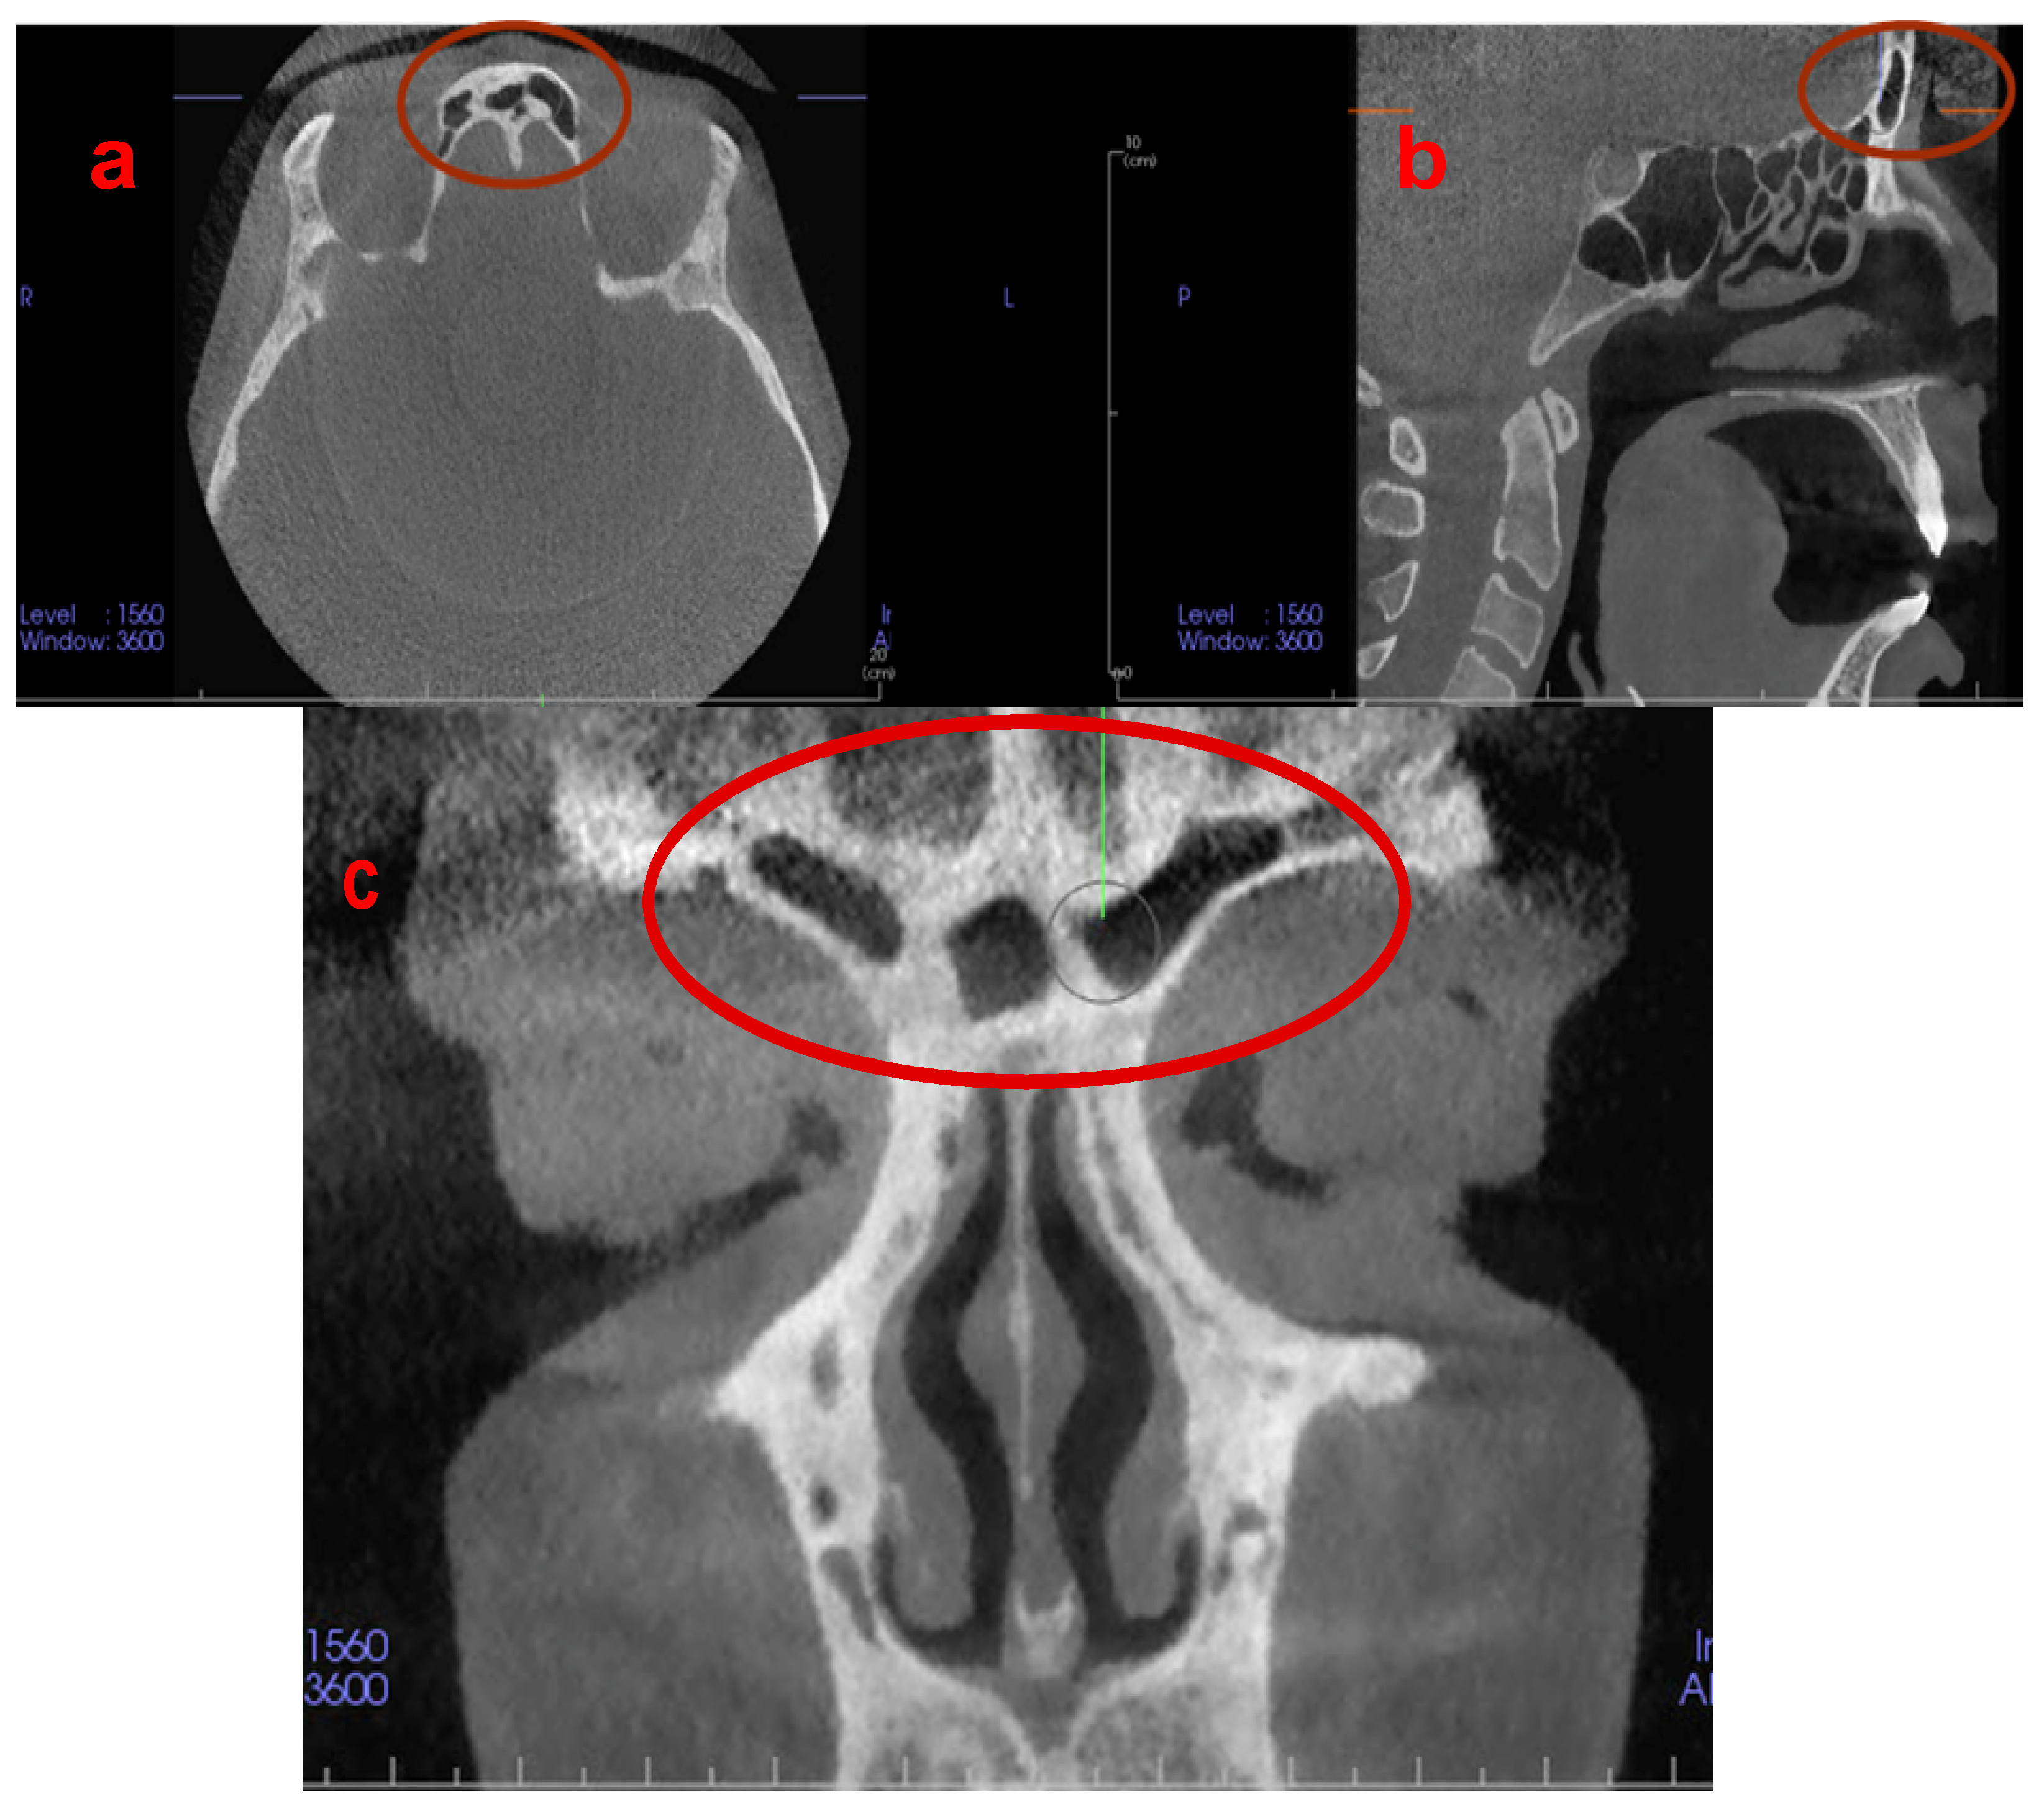

In recent decades, the morphology of frontal sinuses (FS) has emerged as a crucial tool in forensic dentistry due to its dimensional stability in adulthood [8]. The FS are protected from injuries as an internal bony structure and even exhibit variations in monozygotic twins [9,10]. FS are bilateral air-filled cavities, and their initial development occurs at the age of 2 or 3 years. The FS can be clearly visualised radiographically at the age of 5 or 6 years, and their final shape is completed and fully developed at the age of 20 years [8,11,12] (Figure 1).

Figure 1.

(a) Axial, (b) sagittal, and (c) coronal CBCT images demonstrating the unique and individualised architecture of the frontal sinuses.